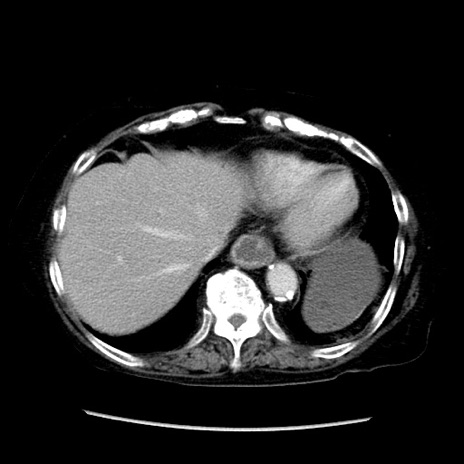

冠状断像